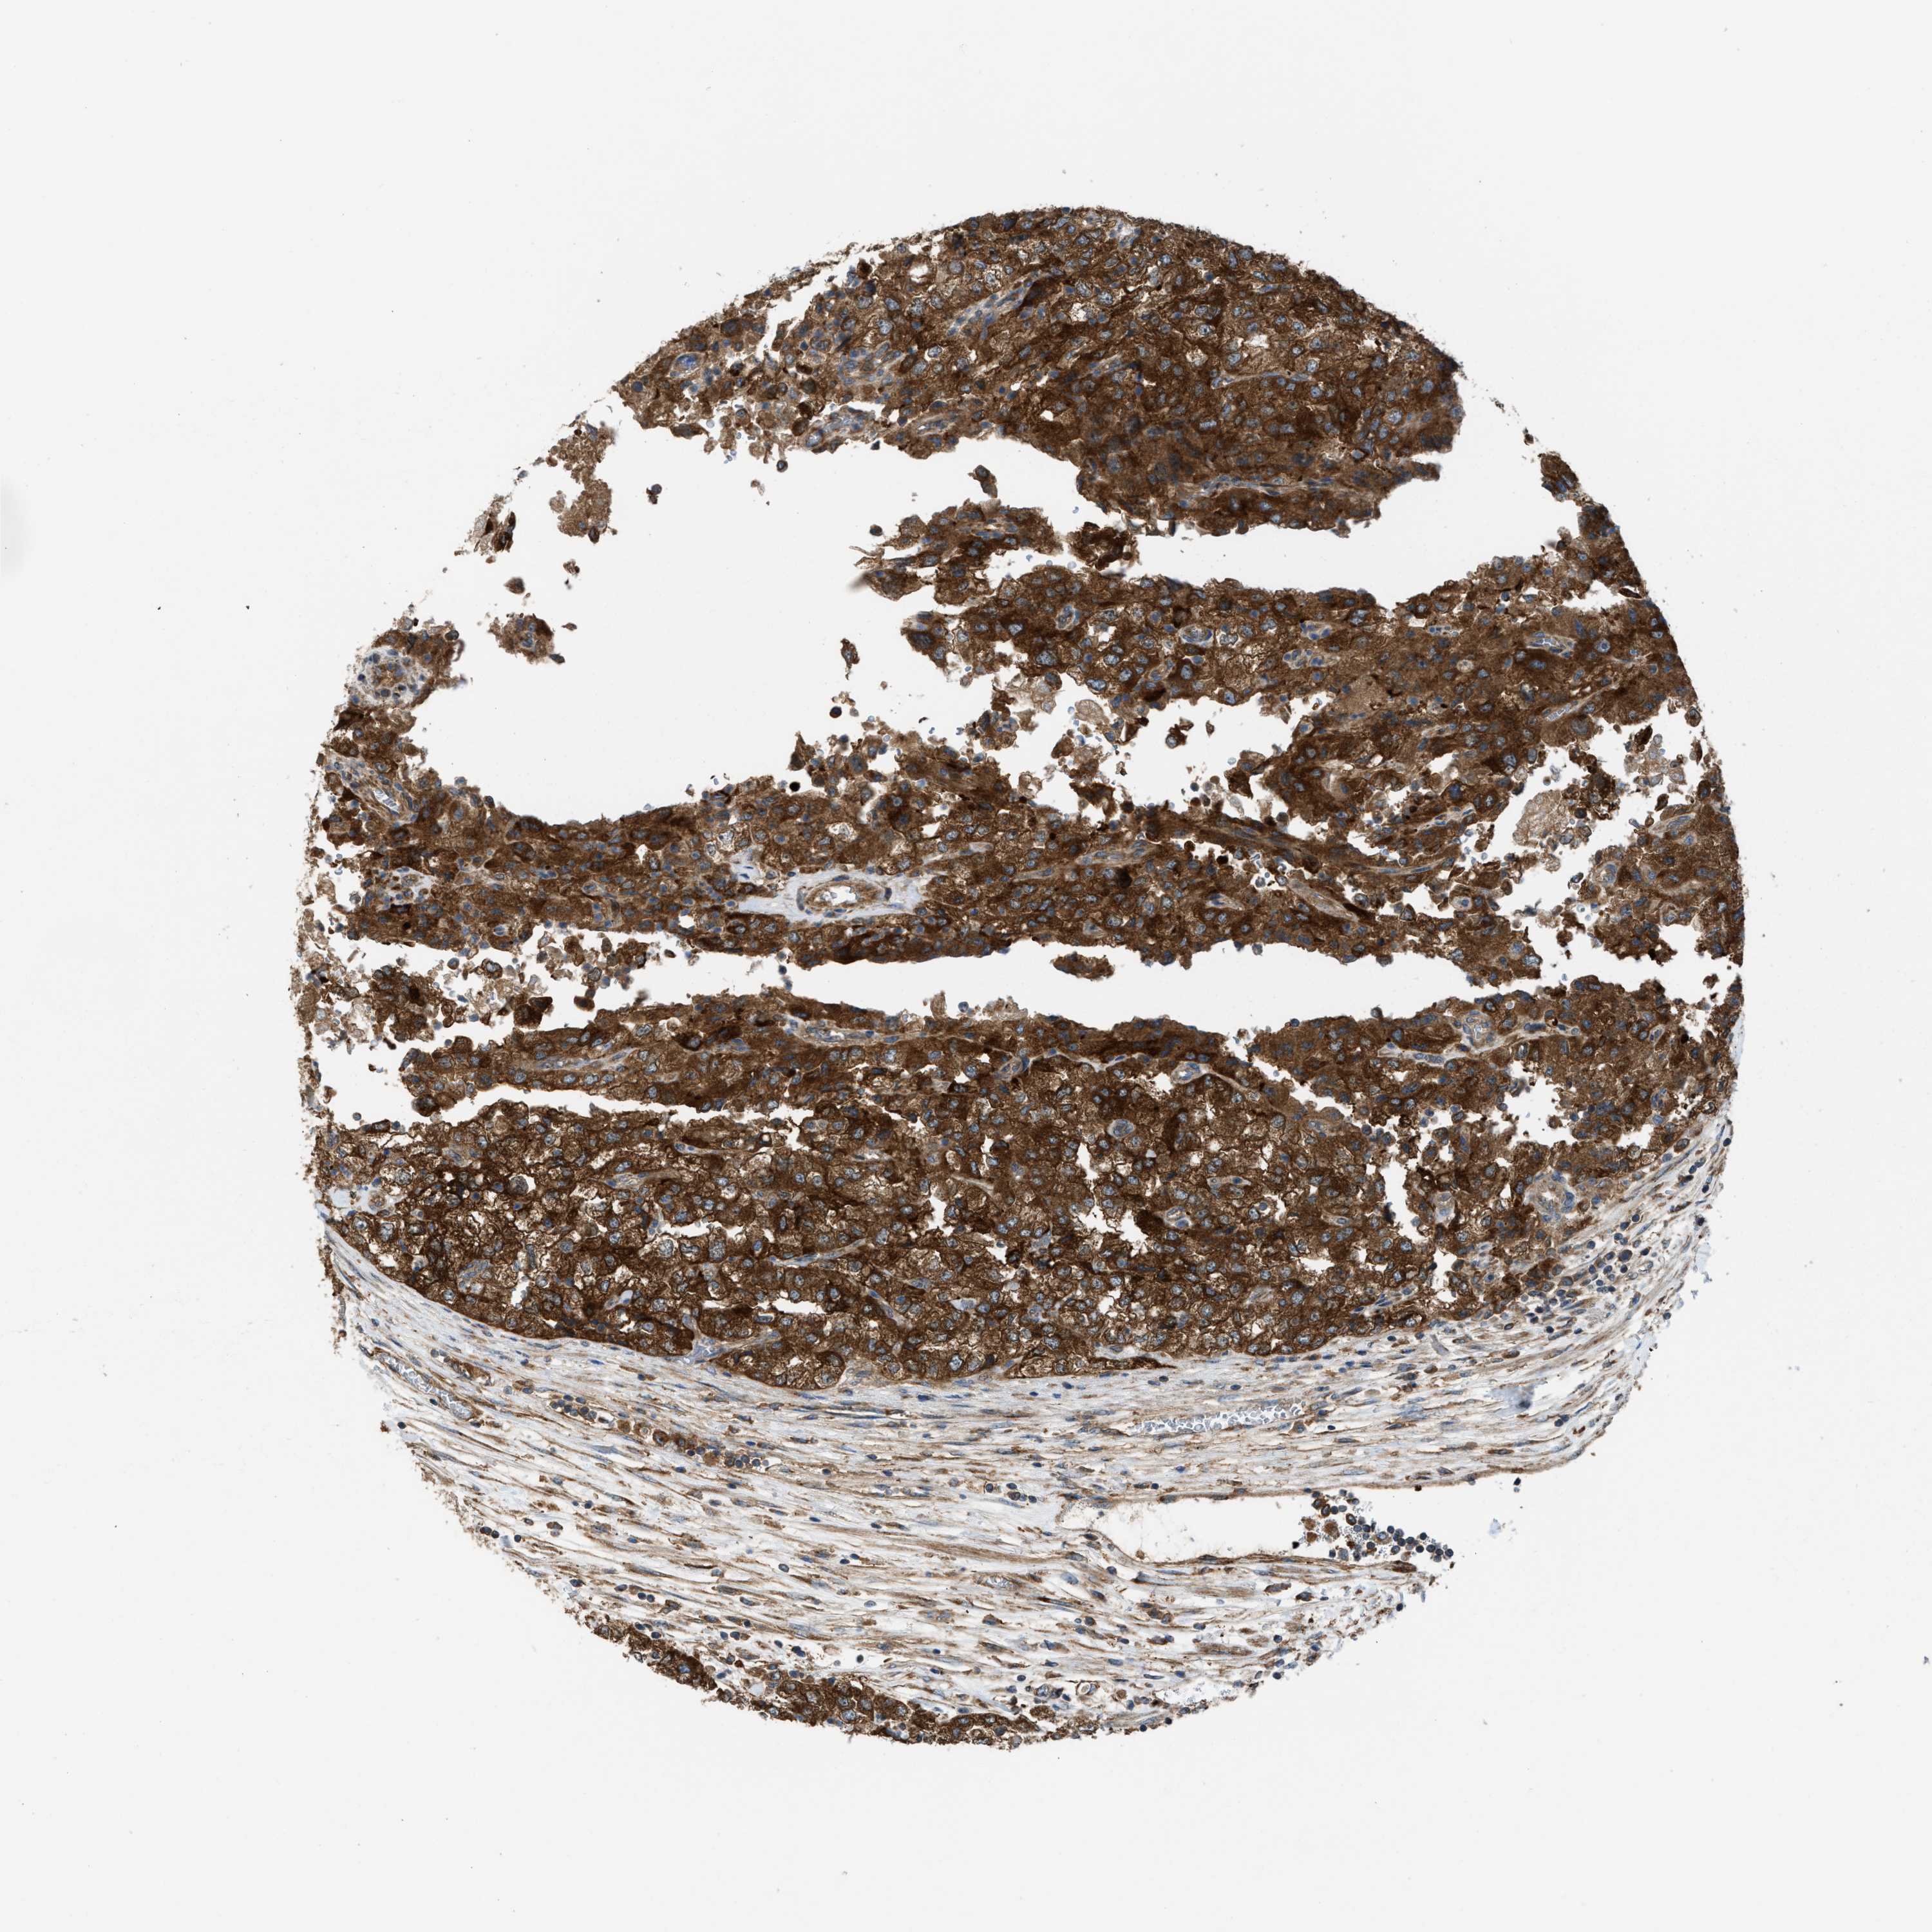

KIDNEY RENAL CLEAR CELL CARCINOMA (VALIDATION) - Interactive survival scatter ploti

The Survival Scatter plot shows the clinical status (i.e. dead or alive) for all individuals in the patient cohort, based on the same data that underlies the corresponding Kaplan-Meier plots. Patients that are alive at last time for follow-up are shown in blue and patients who have died during the study are shown in red.

The x-axis shows the expression levels (FPKM) of the investigated gene in the tumor tissue at the time of diagnosis. The y-axis shows the follow-up time after diagnosis (years). Both axes are complimented with kernel density curves demonstrating the data density over the axes. The top density plot shows the expression levels (FPKM) distribution among dead (red) and alive patients (blue). The right density plot shows the data density of the survived years of dead patients with high and low expression levels respectively, stratified using the cutoff indicated by the vertical dashed line through the Survival Scatter plot. This cutoff is automatically defined based on the FPKM cutoff that minimizes the p-score. The cutoff can be changed by dragging the vertical line or by entering a cutoff value in the square labeled "Current cut-off".

Under the Survival Scatter plot the p-score landscape (black curve; left axis) is shown together with dead median separation (red curve; right axis). Dead median separation is the difference in median mRNA expression between patients who have died with high and low expression, respectively. It is calculated as follows: median FPKM expression of dead patients with high expression - median FPKM expression of dead patients with low expression. This is intended to aid the user in visually exploring custom cutoffs and the associated p-scores and dead median separation.

Individual patient data is displayed and can be filtered by clicking on one or more of the category buttons on the top of the page. Categories describing expression level and patient information include: high, low, alive, dead, female, male and tumor stages. The scale of the x-axis can be toggled between linear and log-scale by clicking on the "x log" button. Mouse-over function shows TCGA ID, patient information and mRNA expression (FPKM) for each patient.

& Survival analysisi

Kaplan-Meier plots summarize results from analysis of correlation between mRNA expression level and patient survival. Patients were divided based on level of expression into one of the two groups "low" (under cut off) or "high" (over cut off). X-axis shows time for survival (years) and y-axis shows the probability of survival, where 1.0 corresponds to 100 percent.

ZNF614 is validated prognostic, high expression is favorable in Kidney Renal Clear Cell Carcinoma (validation)

Best expression cut offi

Based on the FPKM value of each gene, patients were classified into two groups and association between prognosis (survival) and gene expression (FPKM) was examined. The best expression cut-off refers the FPKM value that yields maximal difference with regard to survival between the two groups at the lowest log-rank P-value. Best expression cut-off was selected based on survival analysis .

When clicking on this number, the vertical dashed line indicating cut-off, the interactive survival plot, and the Kaplan-Meier curve will be adjusted to show results based on the best expression cut-off.

: 5.61

TCGA RNA samplesi

RNA-seq data is reported as average FPKM (number Fragments Per Kilobase of exon per Million reads), generated by the The Cancer Genome Atlas (TCGA) .

Normal distribution across the dataset is visualized with box plots, shown as median and 25th and 75th percentiles. Points are displayed as outliers if they are above or below 1.5 times the interquartile range. FPKM values of the individual samples are presented next to the box plot.

Average pTPM 5.4

Number of samples 100